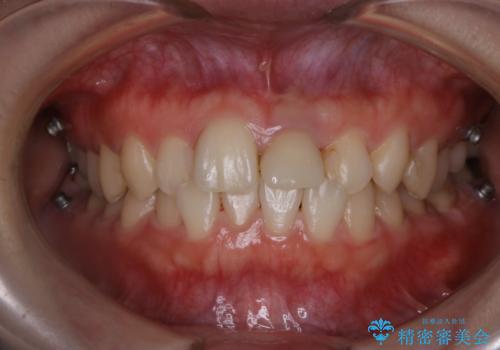

インビザラインのアタッチメントをつける前にPMTC

- インビザラインでの矯正治療中で、アタッチメントの設定前にきれな状態にしたいとのことでした。PMTC30分コースを行いました。

マウスピース矯正インビザライン治療では、歯の表面にアタッチメントという突起を設定します。(アタッチメントは歯の動きを効率的に移動するためのものです)

アタッチメントの設定時に、プラークや歯石・着色がついていると精密に付かないことや、外れやすくなることがあります。

PMTCを行い、専門的な機械でしっかりと汚れを除去してからアタッチメントの設定をすることがおススメです。